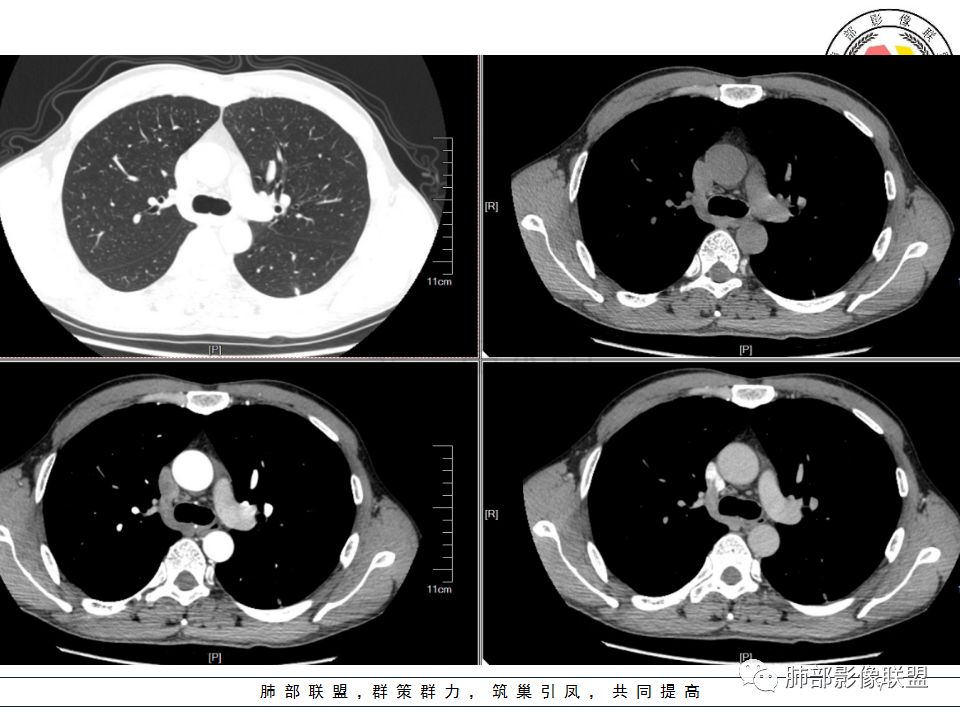

南边:问一个问题:支气管在这里堵了吗

Shelia:堵了,而且支气管壁增厚了。

Coke with ice:我认为堵了,不倾向于肿瘤的堵塞。对于这个病例来说,结核的爬行和肿瘤的堵塞鉴别点不清晰。

南边:这是支气管吗?

张立:是

南边:

远端有支气管显示,提示支气管局部没有堵塞,这个近端的看起来堵塞的支气管可能是假象。

这是我首先把它定在炎性,附近有一些小卫星灶,我还是倾向结核放在前面,待排恶性肿瘤。刚才有老师考虑隐球,这个就不太支持,因为它的长轴是沿支气管过来的,这明显就不是隐球特点。附近有一些小卫星灶,我还是倾向一个结核的可能性大。